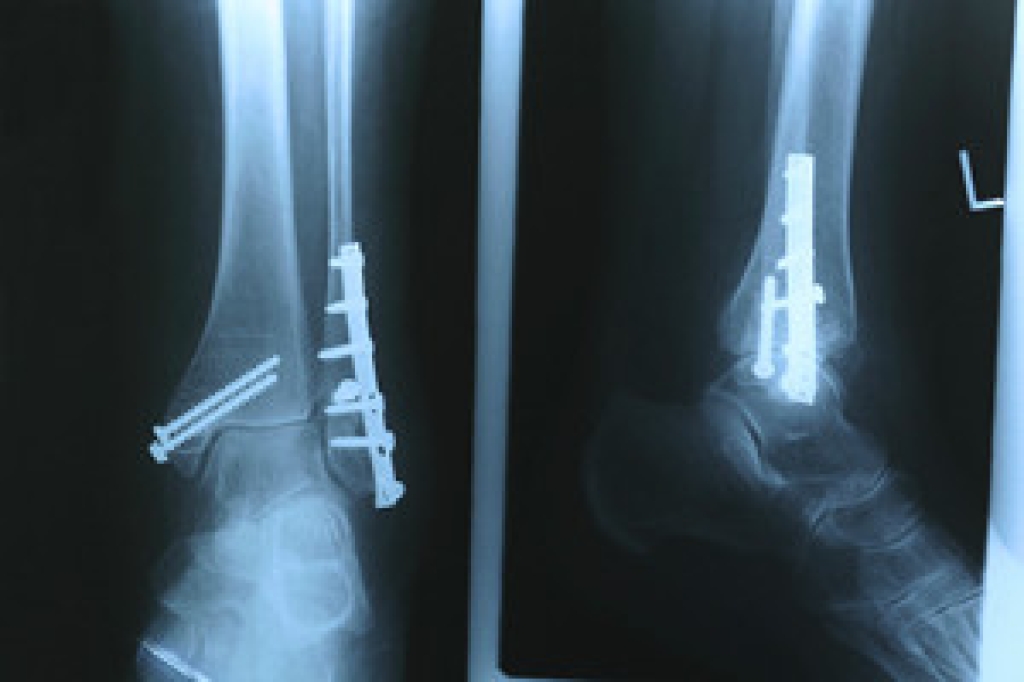

Severe toe fractures may be treated with a splint, cast, and in some cases, minor surgery. Due to its position and the pressure it endures with daily activity, future complications can occur if the big toe is not properly treated.